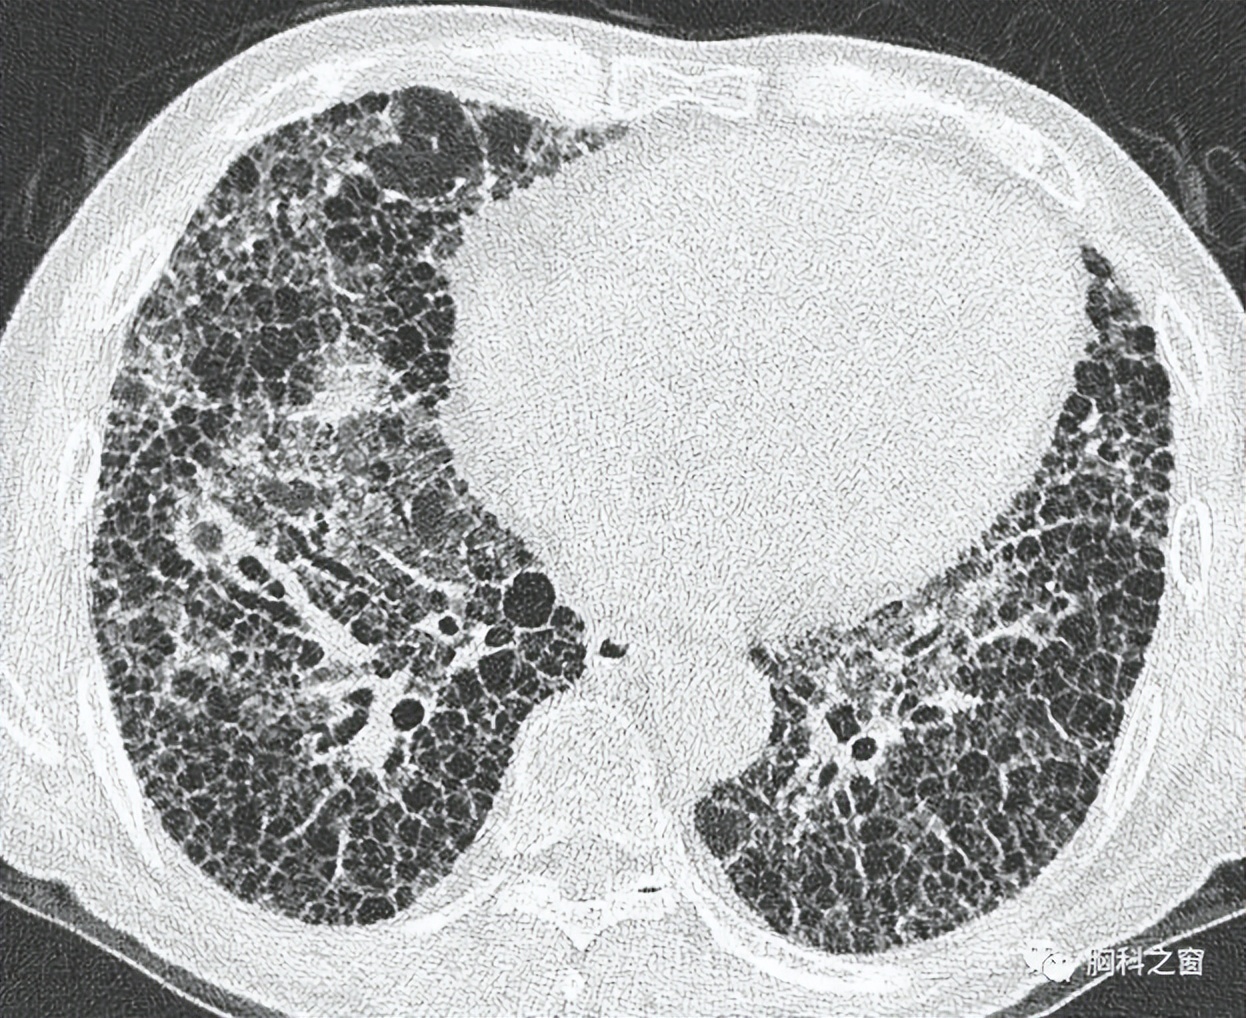

肺间质纤维化是一种肺间质的炎症性疾病,病变主要发生在肺间质、肺泡上皮细胞或肺血管部位。一般明确的致病因素有,过量吸入了空气中的粉尘、烟尘、二氧化硫等杂质而无法排出;病毒、细菌等有害物质的感染;药物、放射导致的损伤等。

肺间质纤维化患者的临床表现为干咳、进行性呼吸困难,或者四肢末端紫绀、鹰爪指、杵状指,严重者会出现消瘦、乏力、胸部憋闷等症状,最终呼吸衰竭而死。由于肺间质纤维化早期临床症状不明显。很多患者容易在不经意间,使病情从早期转变到中晚期的肺间质纤维化。